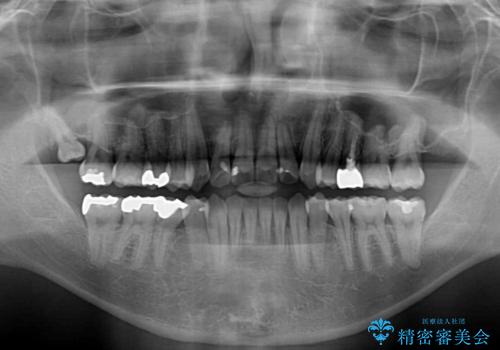

舌の突出癖の影響か、下顎前歯がなかなか整わず、治療期間は予定よりも長期間となりました。

舌突出癖改善のトレーニングの重要性を認識することとなりました。